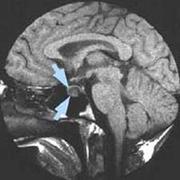

انجام 4 مورد عمل جراحی تومور غده هيپوفيز از طريق بينی